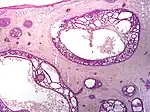

Nodular basal-cell carcinoma

Nodular basal-cell carcinoma (also known as "classic basal-cell carcinoma") accounts for between 50% and 80% of all BCC.[2] It most commonly occurs on the sun-exposed areas of the head and neck.[2] Histopathology shows aggregates of basaloid cells with well-defined borders, showing a peripheral palisading of cells and one or more typical clefts.[17] Such clefts are caused by shrinkage of mucin during tissue fixation and staining.[18] Central necrosis with eosinophilic, granular features may be also present, as well as mucin. The heavy aggregates of mucin determine a cystic structure. Calcification may be also present, especially in long-standing lesions.[17] Mitotic activity is usually not so evident, but a high mitotic rate may be present in more aggressive lesions.[17] Adenoidal BCC can be classified as a variant of NBCC, characterized by basaloid cells with a reticulated configuration extending into the dermis.[17]

Cleft.